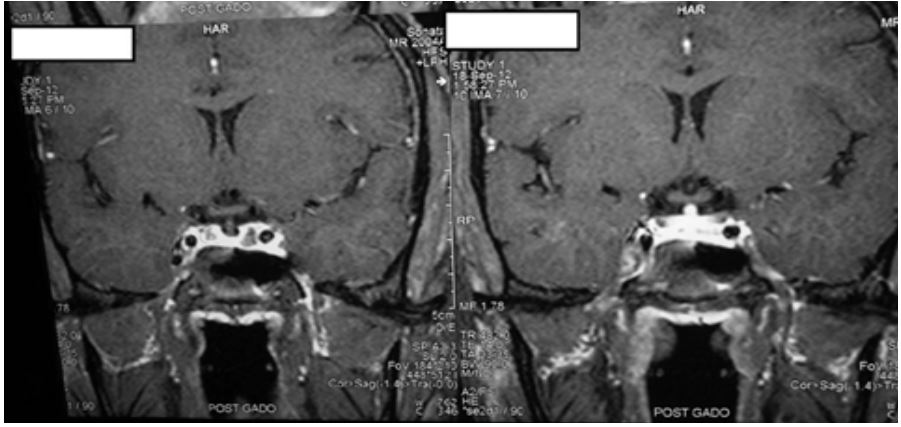

Figure 2: Coronal sections of MRI of the brain and pituitary also revealed small pituitary gland with enhancing infundibular stalk.